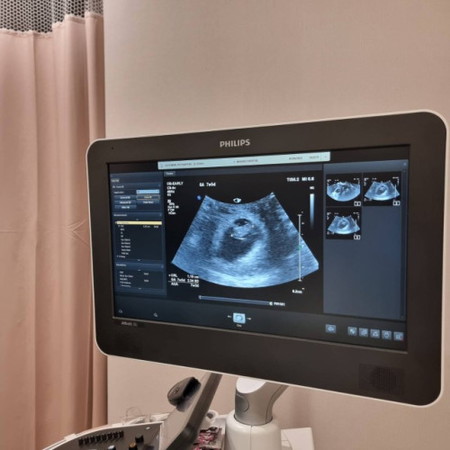

ตั้งครรภ์ได้ 10 สัปดาห์แล้วค่ะ ได้ยินเสียงหัวใจลูกตอน 8 สัปดาห์พรุ่งนี้คุณหมอนัดติดตามการเจริญเติบโตและตรวจนิฟ คุณแม่อายุ 42 ปีท้องแรกธรรมชาติ อ่านของแม่ ๆ คนอื่นที่ต้องหยุดการตั้งครรภ์เพราะเบบี๋ไม่โต กลายเป็นว่าแม่เครียดเองเลยค่ะพรุ่งนี้ต้องลุ้นหลายอย่างเลย แลกเปลี่ยนพูดคุยให้กำลังใจกันนะคะ 🩷